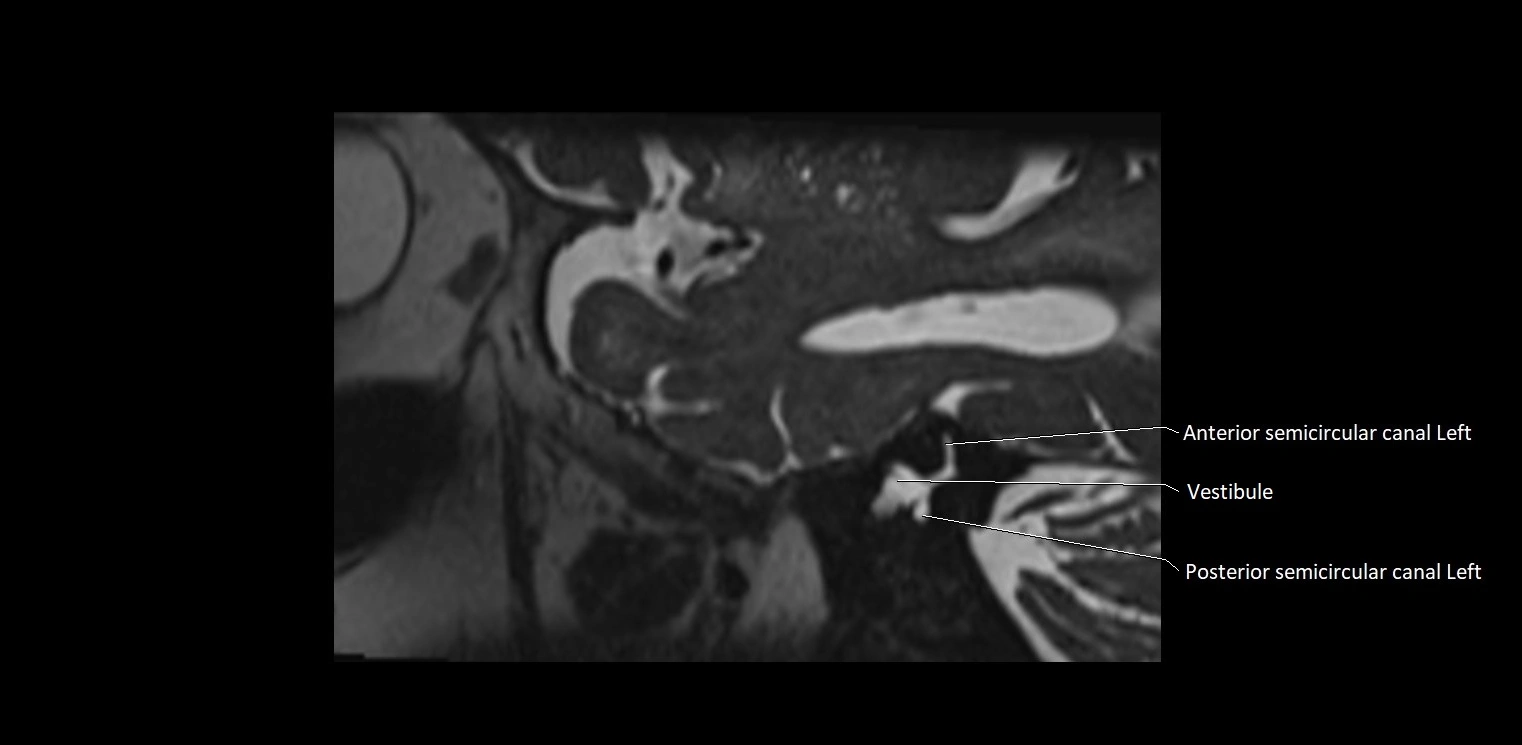

MRI images

image